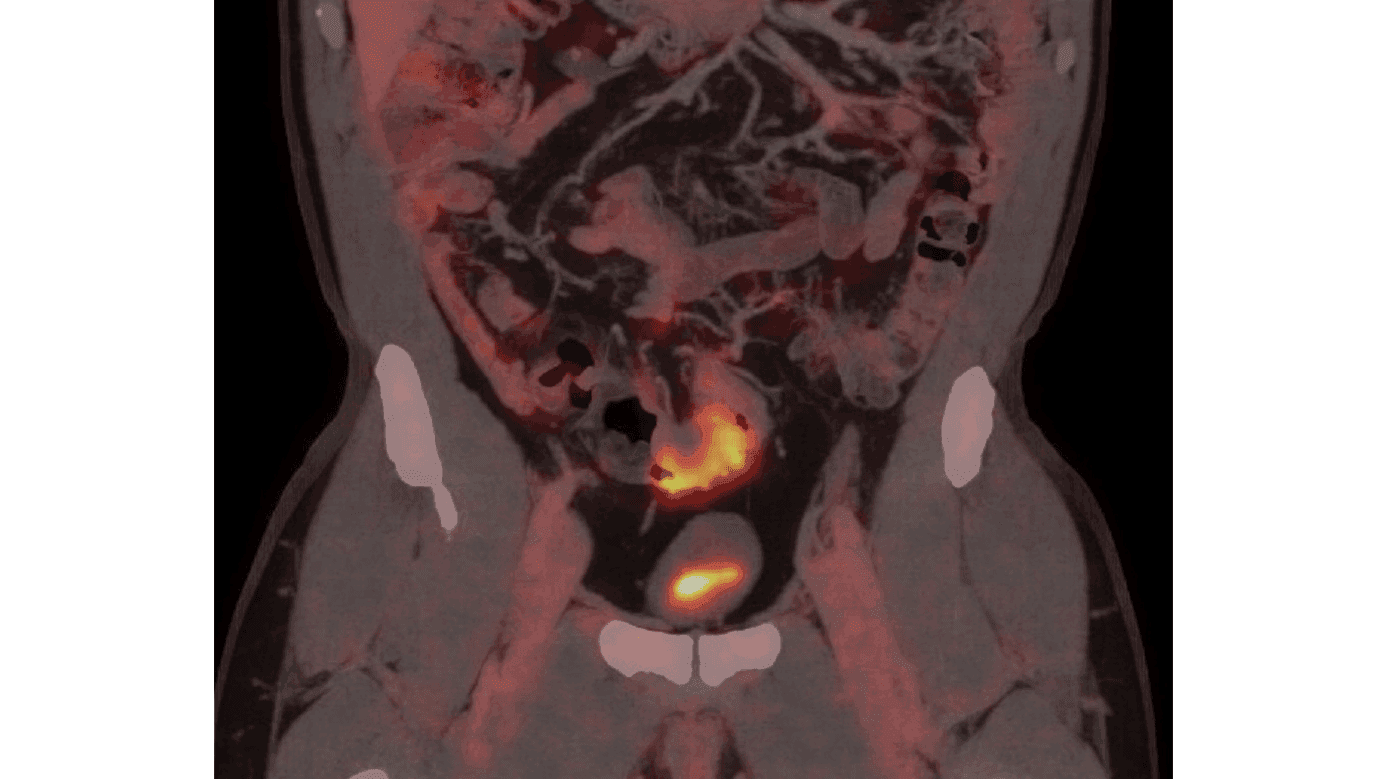

En 54-årig mand, tidligere kendt med højresidig hydrocele, opsøgte egen læge med smerter og hævelse svarende til højre testis. Patienten havde ingen gastrointestinale gener eller B-symptomer. På mistanke om epididymitis henvistes patienten til UL-undersøgelse, hvor der sås en solid tumor i højre scrotum tæt ved caput epididymis. Der blev primært mistænkt et leiomyosarkom, og patienten blev henvist til urinvejskirurgisk afdeling i pakkeforløb. Yderligere UL viste, at tumoren var afgrænset fra testis, men trykkede på denne. Mistanken blev rettet mod en adenomatoid tumor. Med usikkerhed omkring tumorens oprindelse, negative tumormarkører laktatdehydrogenase (LDH), alfaføtoprotein (AFP) og humant choiongonadotropin (HCG), og da CT ikke egnes til at klassificere uklare skrotale forandringer, blev patienten booket til operation. Der udførtes højresidig ingvinal eksploration med frysemikroskopi, hvor der blev fjernet en 1-2 cm stor tumor nær caput epididymis, og der opstod mistanke om mesoteliom, hvorfor der blev gennemført semikastratio. Histologi viste metastase af adenokarcinom, formentlig fra colon. En PET/CT (Figur 1) viste vægfortykkelse i colon sigmoideum, og patienten henvistes til koloskopi og efterfølgende robotassisteret laparoskopisk sigmoideumresektion. Histologi viste adenokarcinom med gennemvækst af peritoneum og metastaser til seks ud af 30 lymfeknuder, klassificeret som T4N2M1-adenokarcinom. Patienten påbegyndte adjuverende kemoterapi med capecitabin og oxaliplatin (CaPox). Ved seneste kontrol den 18.09.2024 var patienten rask uden tegn på recidiv.